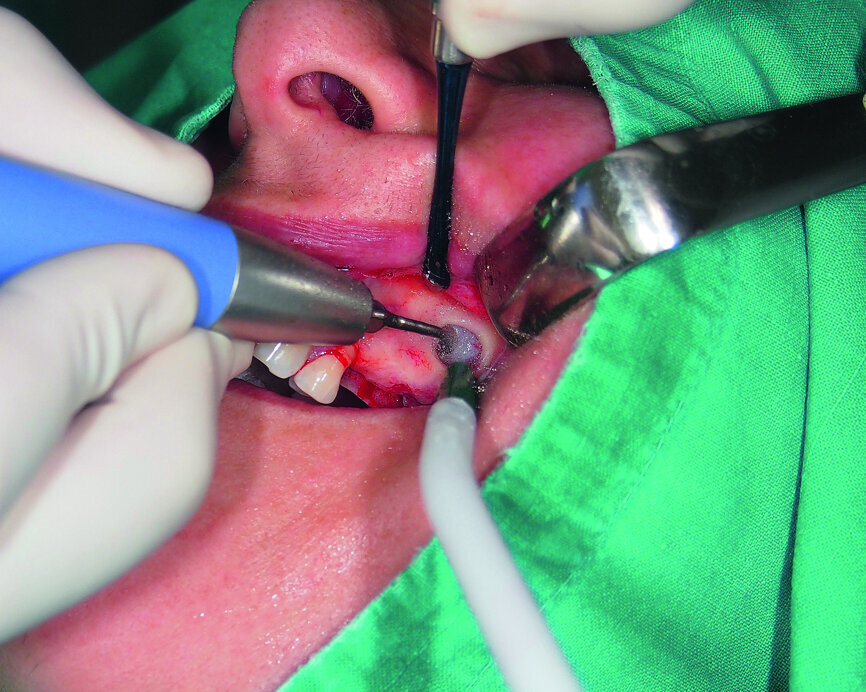

Fig. 5: Lateral window access to the maxillary sinus.

Fig. 6: Facilitation of Schneiderian membrane elevation with a collagenous fleece.

Therefore, we decided to perform a sinus lift by a lateral-wall approach. The Schneiderian membrane was elevated and protected with a collagenous high-density fleece (PARASORB Fleece Genta HD, RESORBA) to allow the placement of a xenogeneic bone graft in the subantral area (Figs. 3–6). Two GC Aadva Standard implants, one of 3.3 mm in diameter and 12.0 mm in length and the other of 4.0 mm in diameter and 10.0 mm in length, were respectively placed in the premolar and molar regions (Figs. 7 & 8). The access window was covered with an absorbable collagenous membrane (PARASORB RESODONT Forte, RESORBA) and the flap was sutured with a polyvinylidene fluoride (PVDF) monofilament suture (RESOPREN 6/0, RESORBA; Figs. 9 & 10).